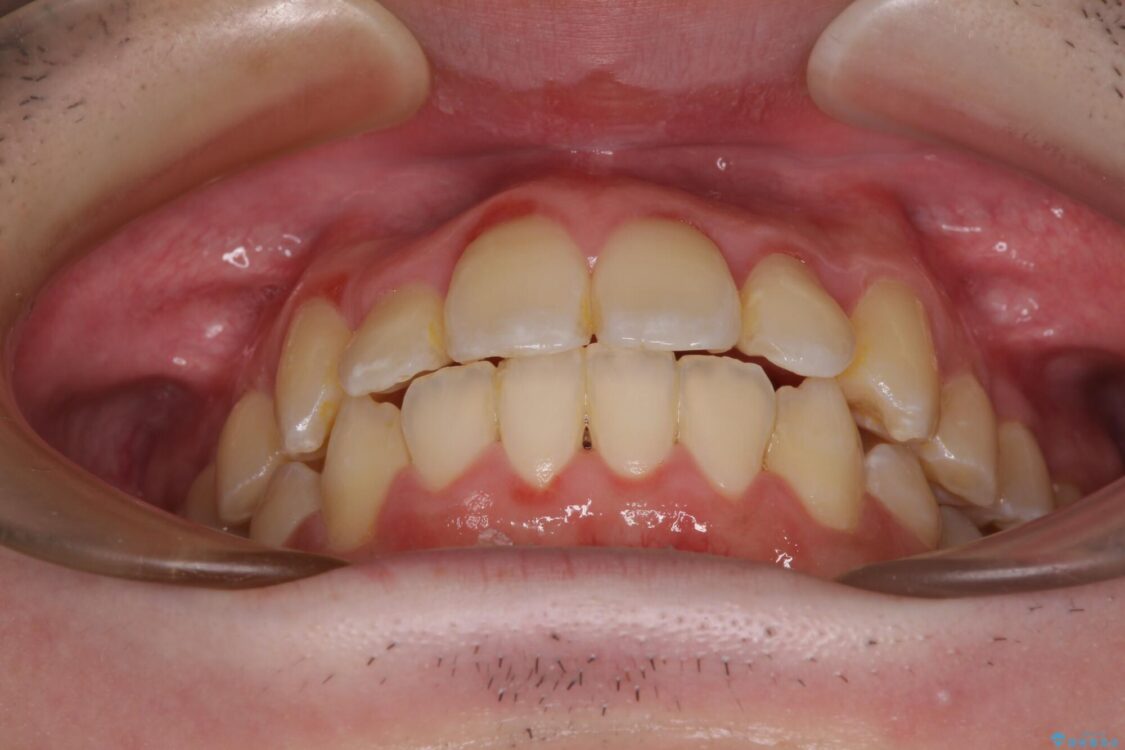

八重歯や奥歯の噛みにくさを気にして来院された患者様です。

前歯のクロスバイトや八重歯の他に、左右最後臼歯のシザーズバイト(鋏状咬合)が認められました。

治療前

• 全顎的なクロスバイト 補助装置を用いてワイヤー矯正 治療前画像